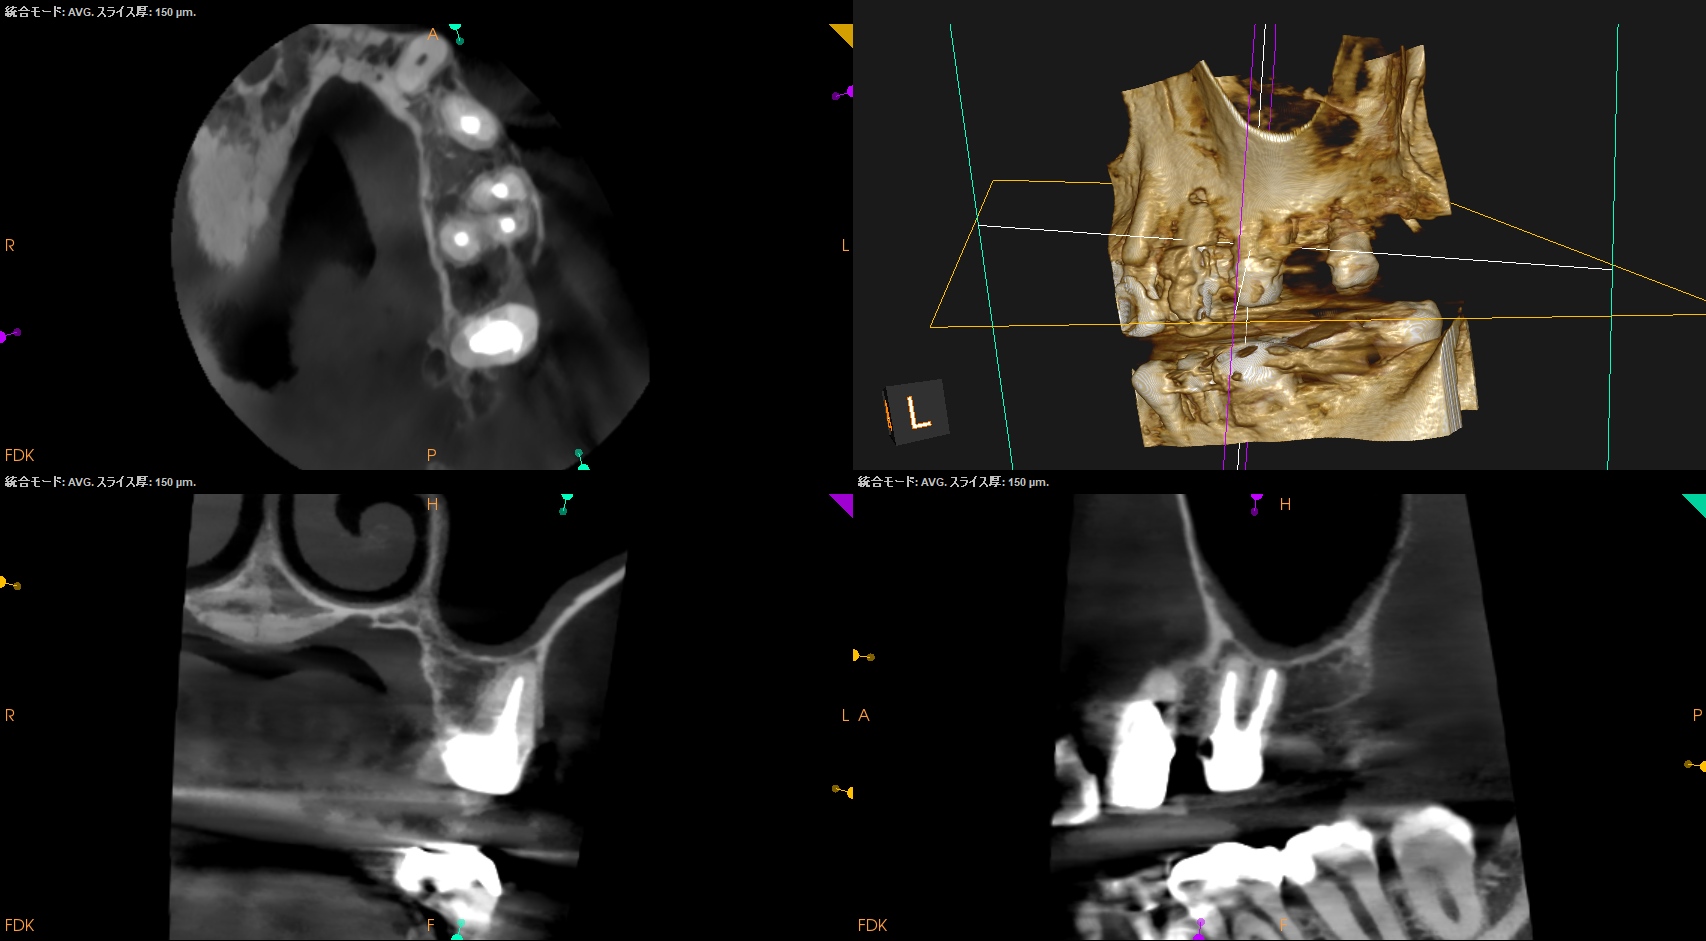

術後にPA, CBCTを撮影した。

#3

MB

DB

P

#14

#16